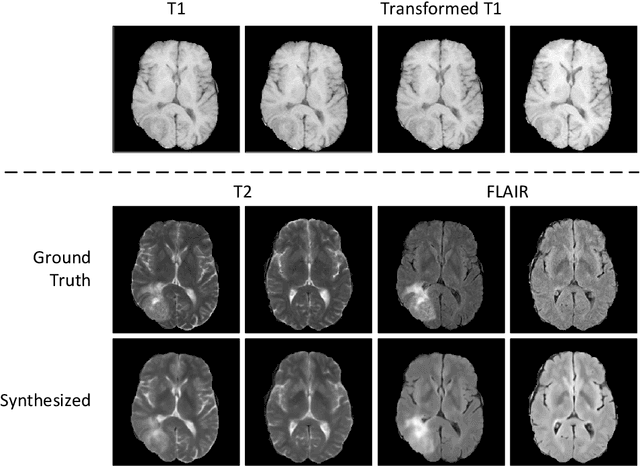

Abstract:Recent studies on T1-assisted MRI reconstruction for under-sampled images of other modalities have demonstrated the potential of further accelerating MRI acquisition of other modalities. Most of the state-of-the-art approaches have achieved improvement through the development of network architectures for fixed under-sampling patterns, without fully exploiting the complementary information between modalities. Although existing under-sampling pattern learning algorithms can be simply modified to allow the fully-sampled T1-weighted MR image to assist the pattern learning, no significant improvement on the reconstruction task can be achieved. To this end, we propose an iterative framework to optimize the under-sampling pattern for MRI acquisition of another modality that can complement the fully-sampled T1-weighted MR image at different under-sampling factors, while jointly optimizing the T1-assisted MRI reconstruction model. Specifically, our proposed method exploits the difference of latent information between the two modalities for determining the sampling patterns that can maximize the assistance power of T1-weighted MR image in improving the MRI reconstruction. We have demonstrated superior performance of our learned under-sampling patterns on a public dataset, compared to commonly used under-sampling patterns and state-of-the-art methods that can jointly optimize both the reconstruction network and the under-sampling pattern, up to 8-fold under-sampling factor.